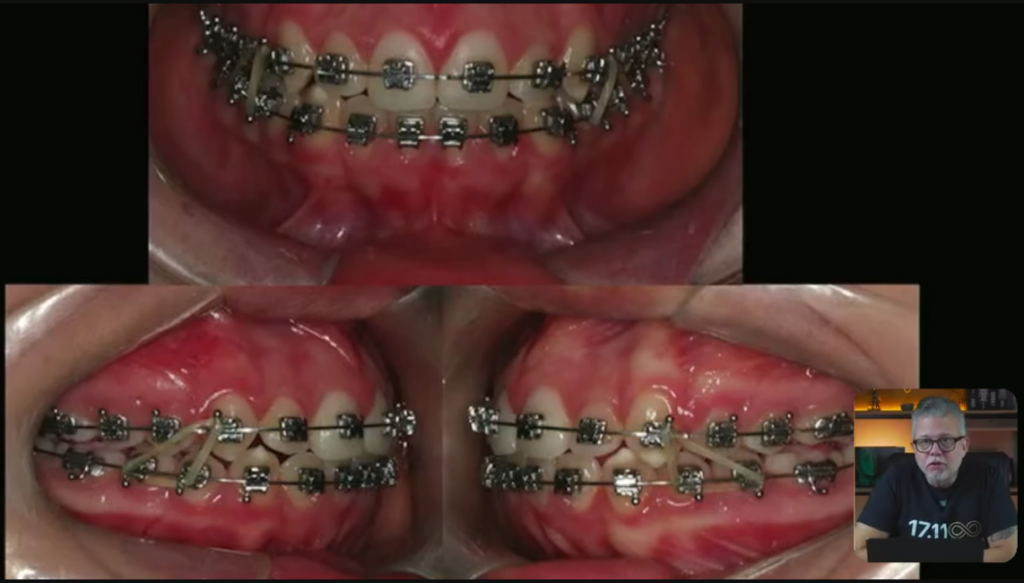

Depois da nossa disjunção:

E aqui a gente utilizou esse bracket:

11 consultas, estava tudo alinhado e nivelado, tiramos o aparelho:

Professor, ficou bom?

Razoável.

Teve alguns detalhes aqui que poderia ter melhorado?

Sim, tem detalhes que poderia ter melhorado aqui.

Quando esse paciente pega essa mandíbula dele, os dentes inferiores, e ele faz o movimento de lateralidade, esse canino inferior, pessoal, ele não toca imediatamente no canino superior.

Então, não faz a desoclusão imediata.

Todo caso que você terminar tem que fazer a desoclusão imediata, porque senão os dentes posteriores vão ficar com um contato ou então um movimento no sentido látero-lateral.

E aí, quando você termina um tratamento como esse aqui, você vai lá e coloca uma contenção.

Esses dentes que vocês estão vendo aqui, super alinhados, então eu coloco essa contenção fixa superior em todos os meus pacientes: